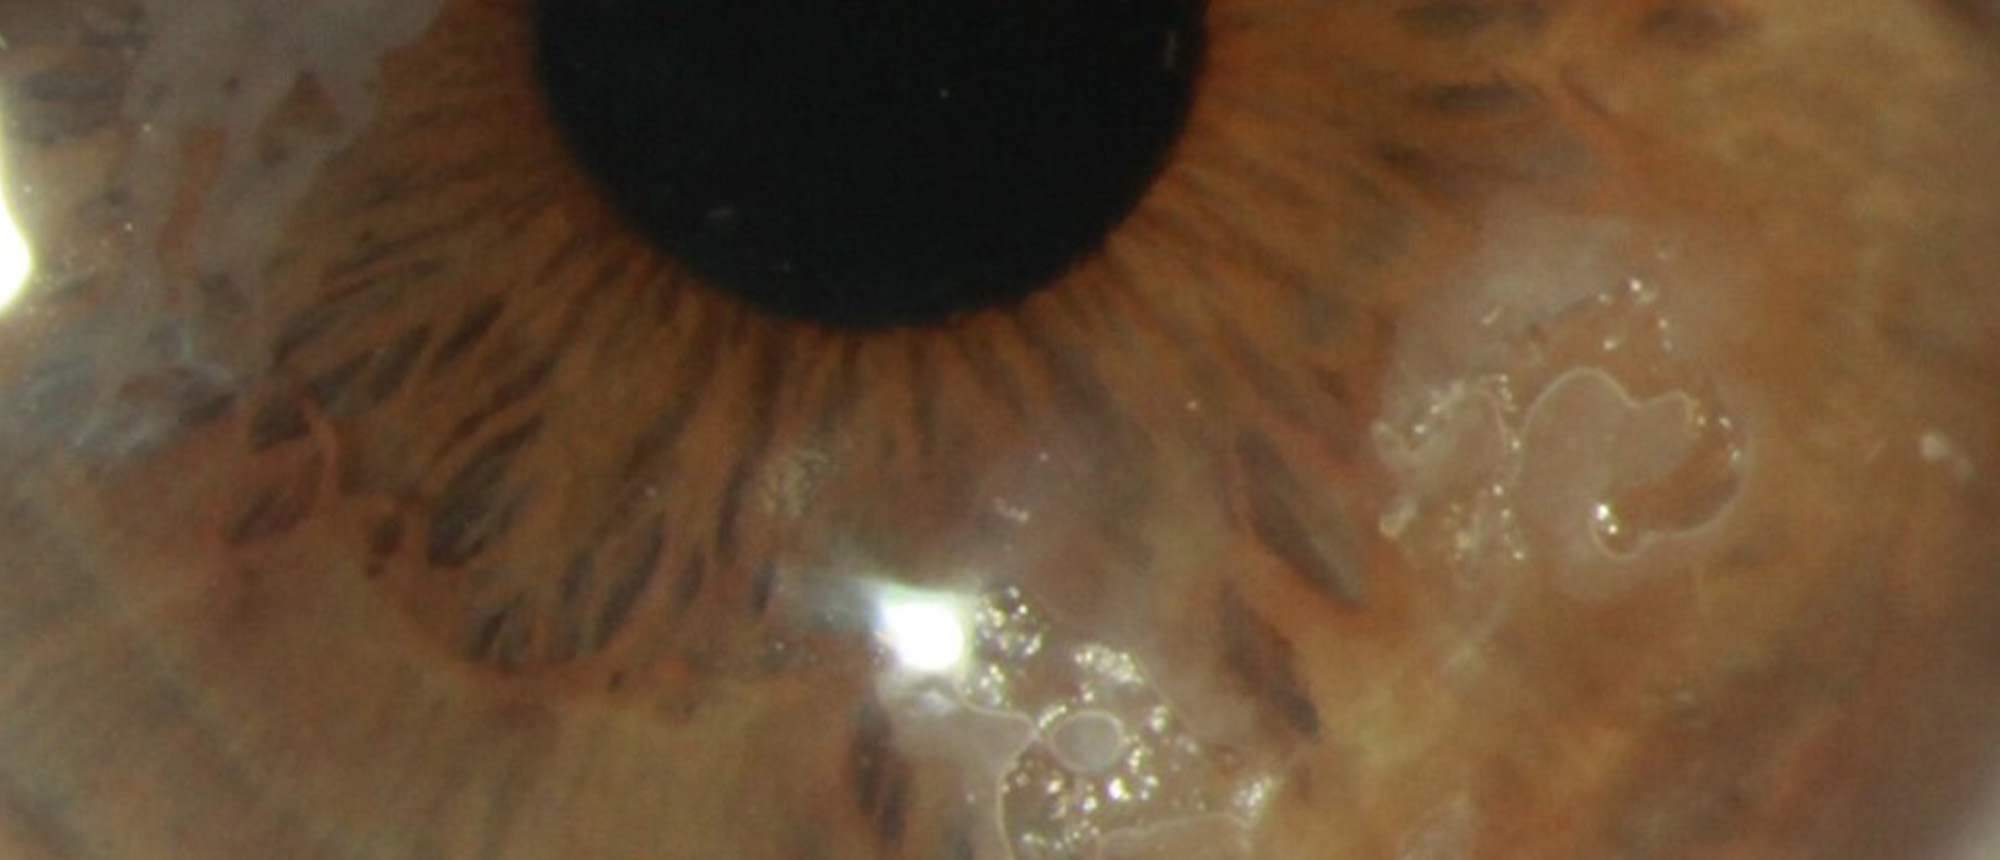

Fusarium Keratitis A patient with no pertinent ocular history presented with 3 months of pain, redness, and blurred vision in the right eye. Visual acuity was HM and slit lamp exam was remarkable for a central infiltrate with feathery irregular margins, significant injection, and a small hypopyon. …